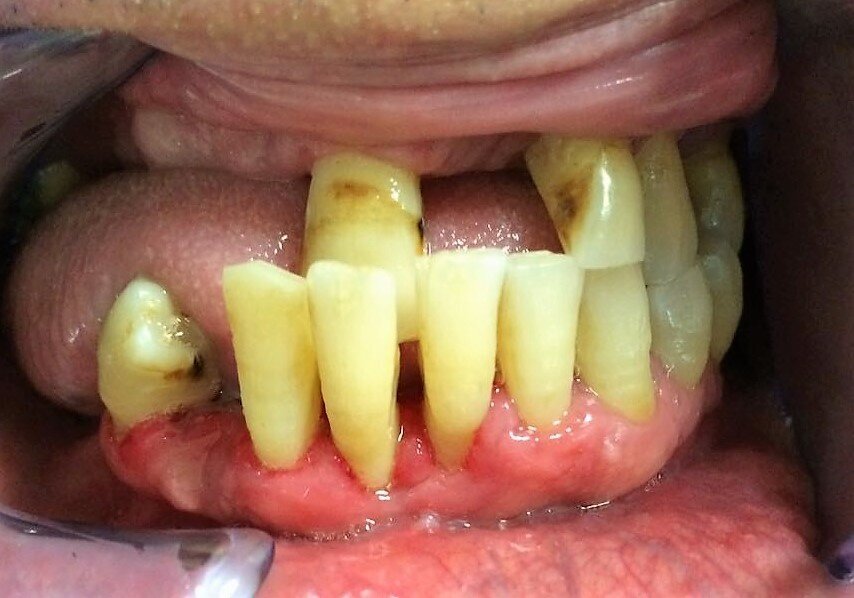

Descriviamo il caso di un paziente maschio di 56 anni con diagnosi di parodontite moderata generalizzata (Figg. 1-3), affetto da Diabete Mellito II in fase di scompenso (HbA1C 8,4%). Oltre alla malattia diabetica diagnosticata da 12 anni, il paziente presentava in anamnesi insufficienza renale, pregresso infarto miocardico acuto e storia di ipertensione arteriosa. I dati anamnestici hanno guidato la scelta dell’iter terapeutico da parte del team odontoiatrico.

In sede di valutazione clinica, il paziente presentava una scarsissima igiene orale e si evidenziavano evidenti segni di flogosi gengivale a causa di notevoli depositi di tartaro sopragengivale e sottogengivale, che rendevano difficoltoso un accurato esame parodontale. Successivamente, si è proceduto alla discussione in team circa la necessità di un intervento terapeutico personalizzato ed efficace che prendesse anche in esame la scarsa disponibilità emotiva e psicologica del paziente ad affrontarlo. Nel presente caso clinico l’adherence è stata considerata come un processo in continuo divenire. Adottando un approccio mutuato dal metodo biopsicosociale5 in una fase preliminare, un primo colloquio è stato svolto con il coniuge del paziente, al fine di instaurare un percorso riabilitativo di salute orale che fosse supportato anche dal caregiver.